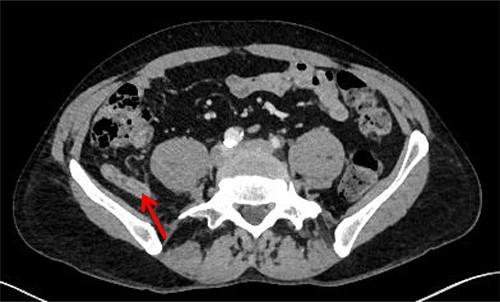

The patient was re-admitted and examination revealed a soft abdomen with localized rebound tenderness in the right iliac fossa. A computed tomography (CT) abdomen was requested and a referral made to the surgical team. The CT scan illustrated AA with the appendix located posterior to the ileo-psoas muscle (Figs 1–3). A diagnostic laparoscopy was performed, which revealed the head of the inflamed appendix herniated posterior to the psoas muscle in a cavity, (~25 mm deep and 10 mm in diameter) that could not be dissected laparoscopically (Fig. 2). Therefore, an uncomplicated open appendectomy was performed and the patient was admitted for post-operative observation. Recovery was uneventful and the patient was discharged without follow-up.

Sagittal CT image. Inflamed appendix (red arrow) positioned between psoas (yellow triangle) and iliacus muscles (green star).